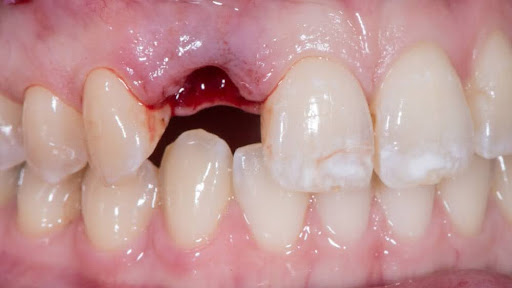

4. Infection or Abscess

A dental infection can weaken the bone and tissue surrounding a tooth, causing it to become loose.

This is a serious condition that requires prompt treatment.

Signs:

- Pain or pressure

- Swelling in gums or face

- Fever or bad taste

Treatment:

- Root canal

- Antibiotics

- Extraction (if necessary)